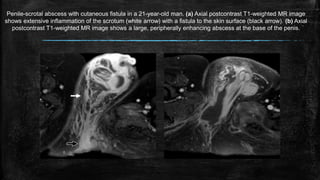

Penile-scrotal abscess with cutaneous fistula in a 21-year-old man. (a) Axial postcontrast T1-weighted MR image

shows extensive inflammation of the scrotum (white arrow) with a fistula to the skin surface (black arrow). (b) Axial

postcontrast T1-weighted MR image shows a large, peripherally enhancing abscess at the base of the penis.

Penile-scrotal abscess withcutaneous fistula in a 21-year-old man. (a) Axial postcontrast T1-weighted MR image shows extensive inflammation of the scrotum (white arrow) with a fistula to the skin surface (black arrow). (b) Axial postcontrast T1-weighted MR image shows a large, peripherally enhancing abscess at the base of the penis.